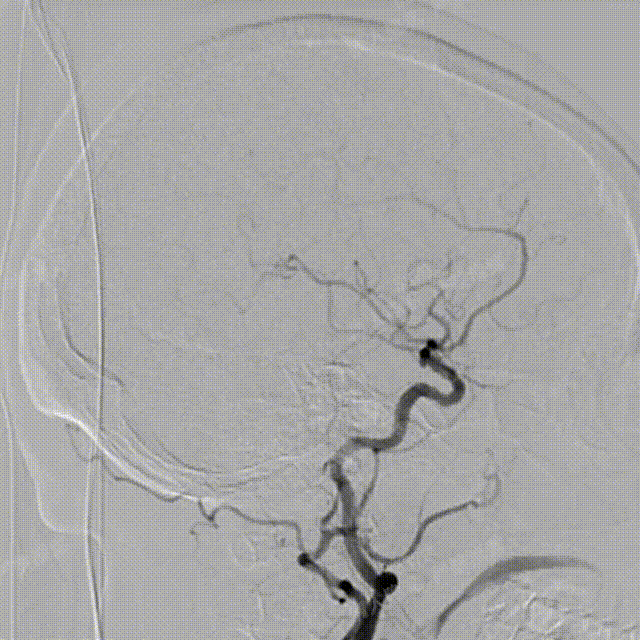

术中DSA造影:左侧颈内动脉正、侧位及3D造影,显示左侧颈内动脉后交通段动脉瘤。

术中DSA造影:右侧颈总动脉3D造影及右侧锁骨下正位造影。

Headway™ 27 156cm微导管内输送FRED 4518血流导向密网支架,系统远端精准定位于预计着陆区以远3-5mm,回撤微导管原位释放支架,头端锚定在颈内末端处。